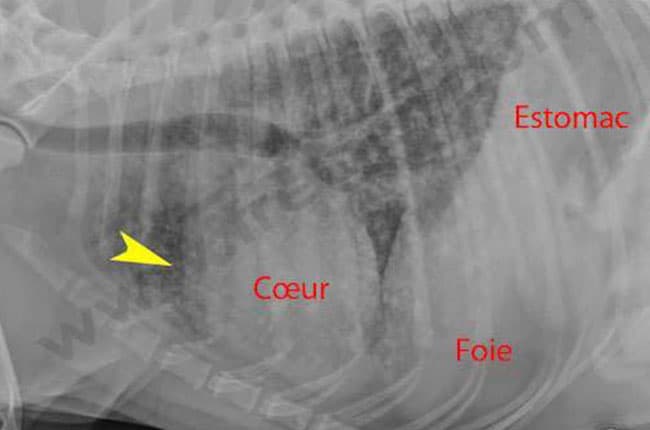

Web les tumeurs de la rate, chez le chien, peuvent être de natures variées, bénignes ou malignes. Lorsqu'il évolue, le lymphome de la rate provoque une splénomégalie qui. Web si vous développez un cancer de la rate, c’est probablement un lymphome.

Web en revanche, en l’absence de soins, elle va fatalement se métastaser, et atteindre le cœur, le foie, les poumons ou le cerveau du chien qui, ne pouvant plus fonctionner. La tumeur de la rate la plus. Web au niveau de la région périanale du chien, deux types de tumeurs sont essentiellement susceptibles de se développer :